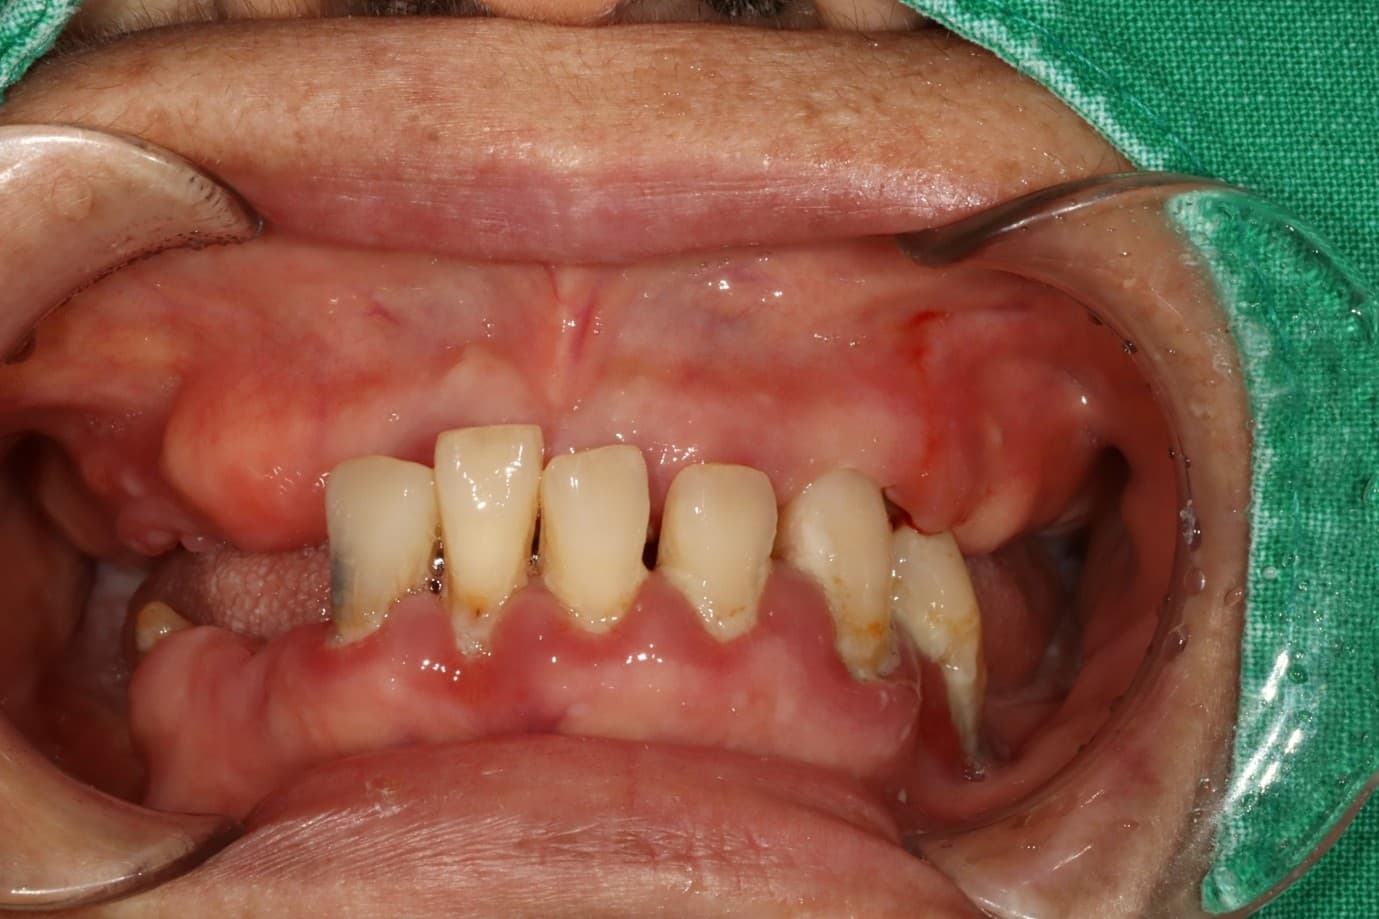

김○님님 치료 사례

구강 사진

치료 전

X-ray